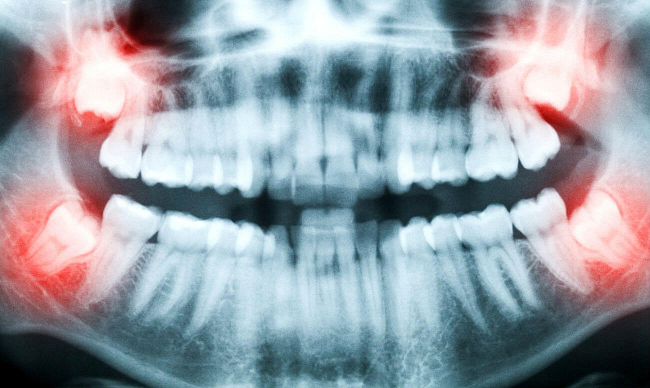

Сложность удаления и лечения зубов мудрости связано с тем, что их корни (3 на верхней и 2 на нижней челюсти) могут быть сращены или переплетены друг с другом. Эти зубы могут расти в щёку, наклоняться, сдвигаться в сторону или не прорезаться, что обусловлено близостью прикрепления связок и жевательных мышц, а также недостатком места в конце зубных рядов. Что же делать, если восьмые зубы доставляют столько хлопот?

Не рекомендуется вырывать зуб мудрости без проведения информативного качественного рентгеновского обследования. Даже при внешнем виде обычного зуба, восьмерка, имеет несколько подводных камней. Это могут быть искривленные корни, которые встречаются и при нормальном росте восьмого зуба, создавая определенные трудности для его удаления.

С помощью рентгеновского обследования можно определить число корней зуба мудрости и их строение.

При последовательном извлечении корней, стоматолог может знать, сколько их должно быть всего и какая у них форма.

Эффективен этот метод и при определении направления роста восьмого зуба. Самым распространенным и полноценным считается снимок, сделанный на ортопантомографе. Это цифровой рентген аппарат, который выполняет рентгеновские обзорные снимки полости рта.

После этого снимок обрабатывается таким же образом, как и цифровое изображение. Данная процедура позволяет достичь максимальной информативности. На подобном снимке хорошо видны корни зуба, их строение и количество, а также направление роста.

В любом случае с помощью рентгеновского снимка врач может просчитать ход и объем предстоящих действий, подготовить необходимые инструменты и определить точную дату удаления зуба мудрости.